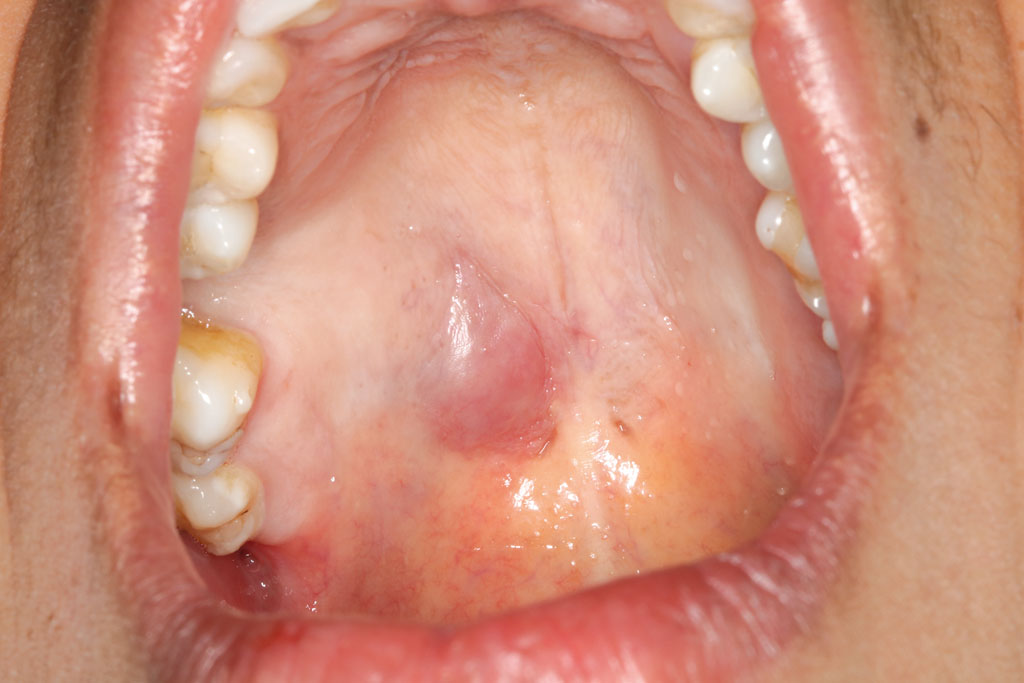

En este trabajo, se presenta un caso en una paciente femenina de 38 años, que acude a la Clínica Odontológica Universitaria (CUO) de la Universidad Europea de Madrid. Se enfoca la rareza de esta neoplasia en relación con su lugar de origen, siendo ésta lateral a rafe medio palatino en tercio dorsal, generado a partir de una glándula salival accesoria palatina. El tratamiento óptimo del ACB es la escisión quirúrgica completa, por lo que se decide realizar una biopsia escisional con márgenes de seguridad para remitir a un estudio anatomopatológico. Fueron tomados en cuenta como diagnósticos diferenciales: adenoma pleomorfo, adenoma canalicular, adenocarcinoma de células basales, subtipo sólido de carcinoma adenoideo quístico y carcinoma de células escamosas de variante basaloide. Es importante realizar una disección completa del tumor para disminuir al máximo la posibilidad de recidivas.